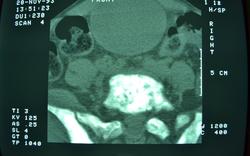

Ургенция, поступил с нижним парапарезом,

В принципе, Вы не предоставили ничего. Иллюстрации я вставила. Предоставлять желательно анонимизированный дайком исследования (залить на файлообменник, сюда дать ссылку). Менее качественный вариант - изображения в аксиалах и реконструкциях в зоне интереса, в костном и мягкотканном окне, если возможно.

Огроменный-здоровенный моч пузырь.... може острая задержка мочи вседствии рака предстательной железы с мтс в кости?